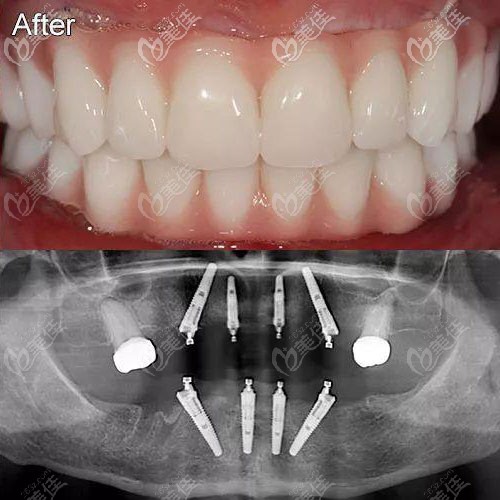

這有北京瑞泰口腔醫(yī)院豐臺(tái)分院的半口種植牙案例圖,大家可看下這種Allon4半口種植修復(fù)效果怎么樣~

(圖片中上面那張是戴上牙冠完成修復(fù)的效果,下面這張是4顆種植體在牙槽骨中的全景片)

4顆種植體是斜形植入,這樣的力學(xué)設(shè)計(jì)可以使半口種植牙受力呈現(xiàn)“拱形”特征,咬合力會(huì)均勻分散在牙床中,便于行使咀嚼功能。